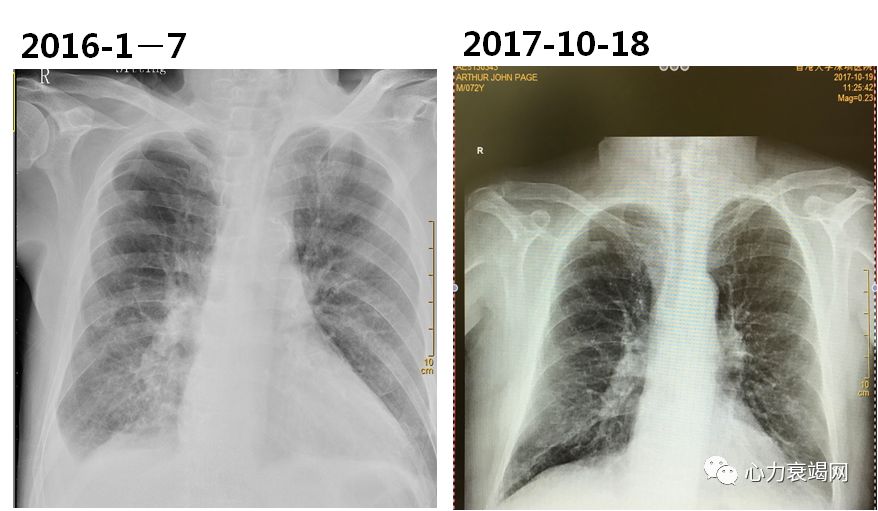

➤ 患者,AJP, 男性,75岁,高加索人

➤ 首诊时间:2015.12.14 呼吸科

➤ 入院时间:2016.1.7

反复咳嗽、咳痰20余年,气喘1月,在呼吸科门诊予化痰、解痉治疗效果不佳,胸部CT示右侧胸腔积液伴右中下肺感染收住院。

半卧位气尚平,二肺呼吸音粗,右肺可及湿罗音。心界向左下扩大,心率118bpm,齐,未及杂音。双下肢不肿。